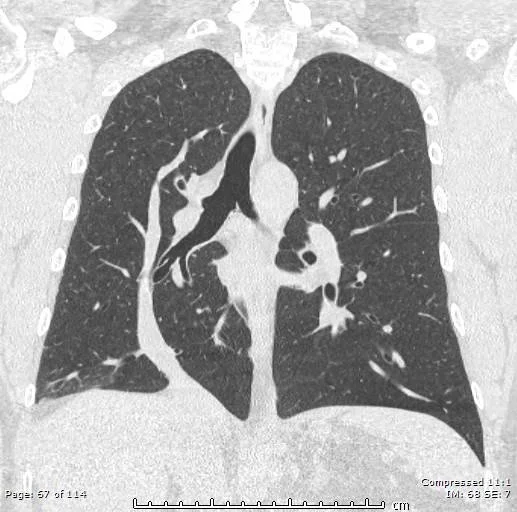

• On CT looks like a tension pneumothorax without the collapsed lung

• Case courtesy of Husam Hussein Yaseen, Radiopaedia.org, rID: 75133